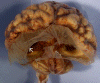

Continuation of gray matter across midline: On a coronal

cut, the gray matter cross over the midline and no corpus callosum is

present and, again, no septum pellucidum is found. Continuation of gray

matter across the midline and a lack of septum pellucidum are two hall mark

features that can aid in easily recognizing lobar or semilobar

holoprosencephaly.